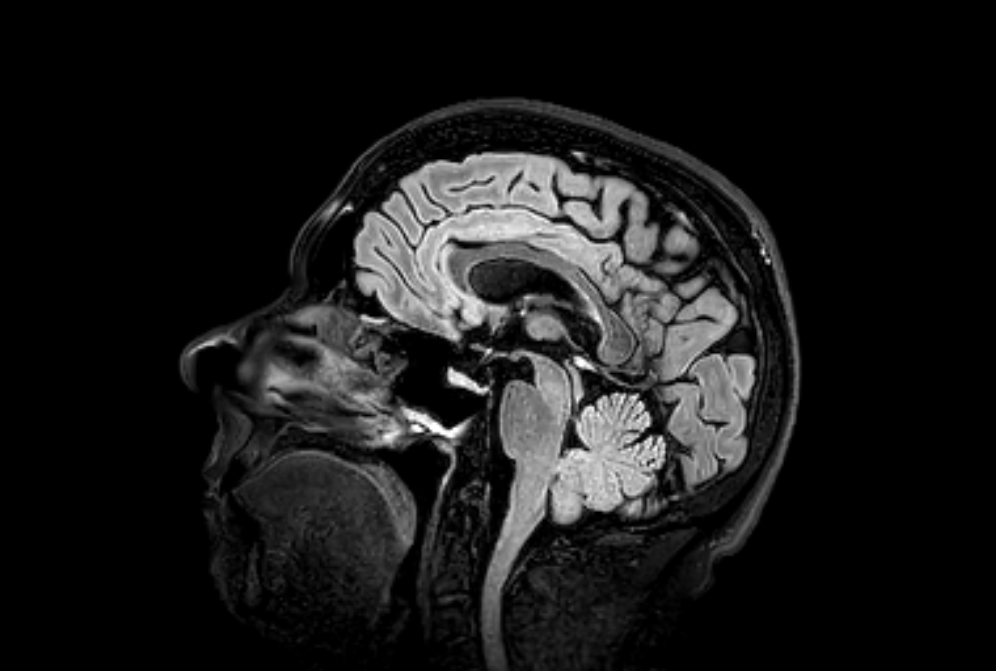

Je n’avais pas de plan précis pour l’organisation spatiale de l’endroit, mais le « bureau » étant à gauche, et la table de travail à droite, cela correspondrait à ce que l’IA me dit sur le rôle de chaque hémisphère du cerveau.

En résumé

Hémisphère gauche : langage, logique, détails, contrôle du côté droit.

Hémisphère droit : créativité, perception spatiale, émotions, traitement global, contrôle du côté gauche.